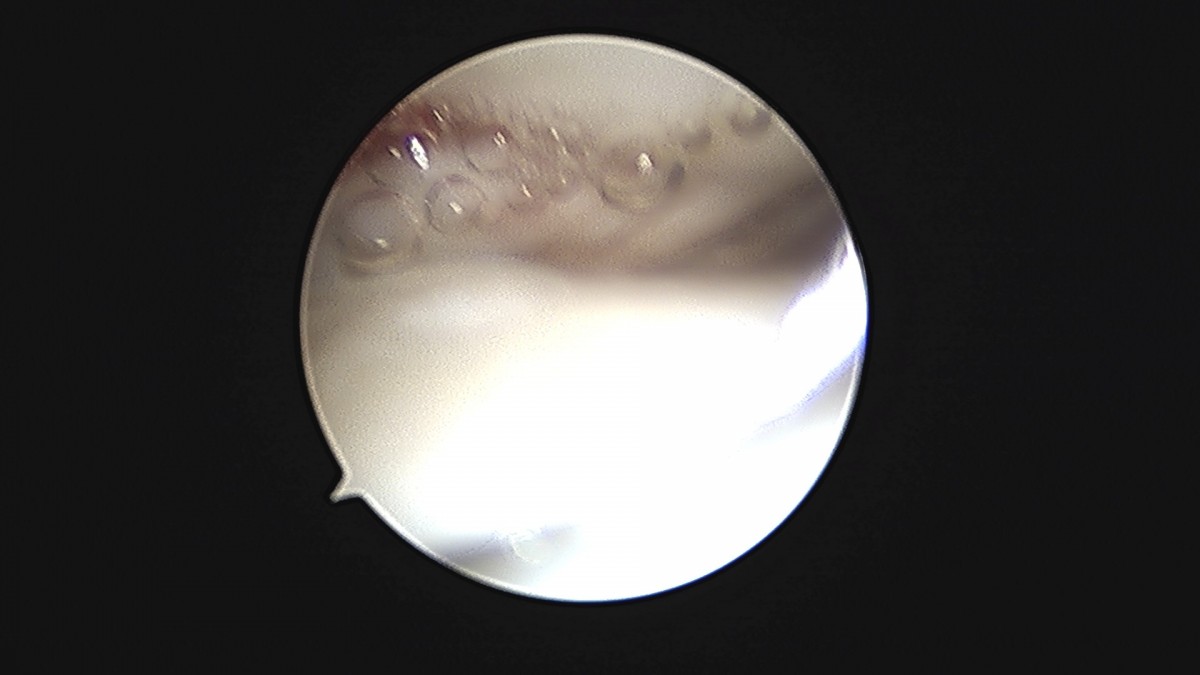

이재상원장님 발목 연골병변 제거술 및 골수 자극술 장경O 환자

작성자 최고관리자 댓글 0건 조회 375회 작성일 25-09-16 16:14